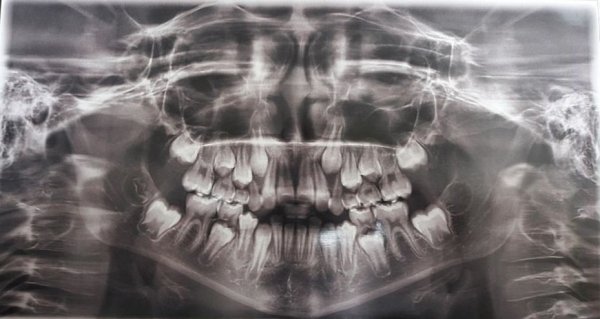

Сложнее бывает ситуация при гипердонтии с нарушением прорезывания. В таких случаях основным методом диагностики является рентген (панорамная рентгенография). На ней можно четко визуализировать все зубные элементы, как нормальные, так и сверхкомплектные, а также их локализацию. Недостатком методики является то, что на рентгене изображение плоское и по нему нельзя охарактеризовать точное взаиморасположение всех зубов и их корневых систем. Поэтому часто пациентам дополнительно проводят компьютерную томографию.

• У жевательной группы зубов зачастую очень сложное анатомическое строение, вероятно полностью прорезался один зуб. Однако, детям так же как и взрослым рекомендовано посещать стоматолога для осмотра регулярно. Обратитесь для осмотра к детскому стоматологу и пройдите рентгенологическое обследование, необходим панорамный снимок для определения состояния зубов, костной ткани и нал

• Для постановки диагноза необходим осмотр врача и ренгеновский снимок (ОПТГ- панорамный снимок, на котором будут видны челюстные кости, все зубы находящиеся в полости рта, а также еще не прорезавшиеся). Зачастую в этом возрасте прорезываются зубы номер 7. Вы можете самостоятельно пересчитать для начала количество зубов у вашего ребенка, их должно быть 14 на нижнем зубном ряду